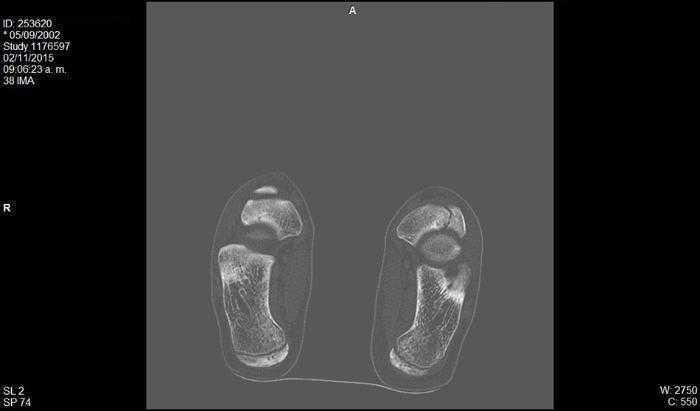

Se realizaron radiografías en proyecciones anteroposterior y oblicua, que mostraron un primer radio corto y esclerosis del escafoides tarsiano con aplanamiento anteroposterior, y un acuñamiento del aspecto lateral dando una morfología en forma de «coma» (Figura 1). En la proyección lateral se observó un trazo de fractura de 45° de inclinación. Con estos hallazgos se suspendió la actividad deportiva y se mantuvo en descarga durante 4 semanas. Se realizaron una resonancia magnética y una tomografía computarizada. La tomografía mostró un trazo de fractura en el escafoides izquierdo y signos de lesión osteocondral (Figura 2). La resonancia mostró un extenso edema intraóseo del escafoides tarsiano, aplanamiento del aspecto lateral, un área con marcada alteración de señal sugestivo de osteonecrosis y una imagen lineal de morfología cóncava que afectaba el aspecto dorsal y lateral del escafoides (Figura 3).

Figura 2. Tomografía computarizada, corte coronal: alteración de la morfología del escafoides tarsiano. Se observa varo del retropié.